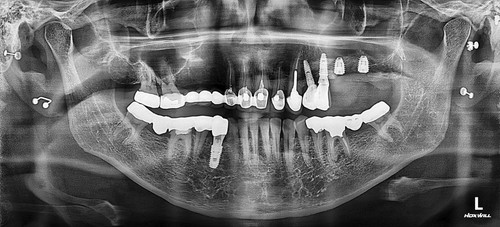

상악동누공폐쇄술이 성공하면 그 다음 단계로는 치조골 이식과 임플란트 식립을 해야 하는데 간혹가다 일반적인 상악동거상술에 비하면 누공이 있었던 부위는 상악동점막과 잇몸살이 유착되어서 힘든 경우가 많습니다. 물론 폐쇄술을 시행하면서 상악동에 뼈이식을 동시에 하는 것도 하나의 방법이 될수 있겠으나 성공했을 때 뿐만 아니라 누공폐쇄술이 실패했을 때를 가정한다면 통상적으로 동시 뼈이식을 시행하기에는 다소 위험성이 따르는 것이 사실입니다. 그래서 이 환자분은 안전하게 단계적으로 진행하기로 하였으며 누공폐쇄술이 성공한 후에 상악동 측방거상술을 시행하였고 이식한 뼈가 충분히 굳은 후에 임플란트를 식립하였습니다.

임플란트를 식립한 후에는 통상적으로는 3개월 후에 임플란트 보철물이 들어가는데 환자분의 사정으로 치과 내원을 못 하셔서 약 5개월 후에 오셨는데 왼쪽 아래 치아의 뿌리 부위의 충치가 발견되어서 아래 치아는 발치하면서 식립하는 즉시식립을 해 드렸습니다.

보통 하악에 임플란트 식립하면 2개월 이내에 치아가 들어가는데 마찬가지로 환자분 사정으로 못 오시다가 6개월이 지나서야 위,아래 임플란트 머리가 들어가고 마무리 할수 있었습니다.